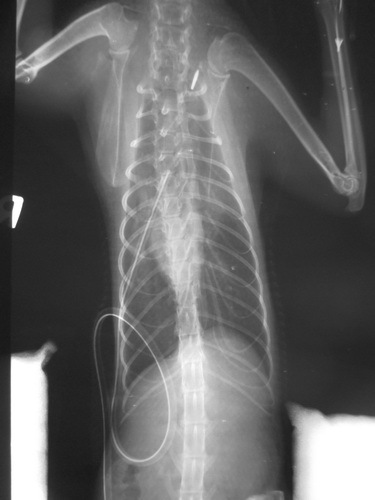

10月17日手術成功,小黑帽狀況還不錯

10月18日接出院自行照顧

照片3是手術前 照片6是手術後動物近況說明: 小黑帽18號回家,還蠻緊張的,沒有像在醫院那麼穩定,會哈氣,19號有穩定些,慢動作的接近他,就不會呼我了,我有用浴巾包住抱著她幫他測了體重是1.8公斤,目前以皇家幼貓當主食,然後每天會再加一餐【貝克牛磺酸錠磨成粉+THOMAS LABS 湯瑪士離氨酸 拌日本AIXIA《MiawMiaw》金妙喵(肽添加-肉狀餐罐)給他吃,所以他目前會吃到4餐,他目前的食慾都很好,喝水量都有超過150CC,他身上黴菌的部分已有好轉35%,想說等她再胖一點,皮膚狀況好一些再進行送養部分,我有在自己的臉書上寫他的一些生活狀況,請朋友分享讓認養進度可以快一點